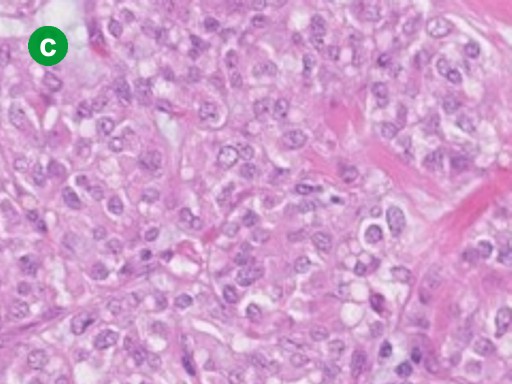

A 26-year-old woman, who had complained of intermittent abdominal pain for 8 years, was referred to our hospital for further evaluation of a pancreatic tumor. She was 159 cm tall and weighed 48 kg. Her pulse rate was 70 min-1 and her blood pressure was 120/80 mmHg. There was no evidence of jaundice. The abdomen was flat and soft but tenderness was present at the upper abdomen. The tumor was not palpable. Other physical examinations were unremarkable. Laboratory data including hematology, blood chemistry including amylase and lipase, and tumor markers including CEA and CA 19-9 were within the reference limits. US imaging showed a pancreatic tumor with solid and cystic components (Figure 1a). A CT scan demonstrated that the well-circumscribed tumor was located in the pancreatic head (Figure 1b). Pancreatograms obtained by MRI and ERCP showed no communication between the tumor and the pancreatic duct. In addition, the ventral pancreatic duct did not communicate with the dorsal pancreatic duct (Figure 2ab). Duodenum-preserving pancreatic head resection was performed [7, 8]. Briefly, the subtotal pancreatic head was resected preserving the bile duct. Reconstitution with drainage of the pancreatic secretion from the remnant pancreas took place with Roux-en Y end-to-side pancreaticojejunostomy. The resected tumor was 50x45x52 mm in size and 50 g in weight, accompanied by hemorrhagic degeneration and surrounded by a red fibrotic pseudocapsule (Figure 3a). Microscopically, the tumor had a cystic component (Figure 3b). The tumor cells were small to intermediate in size with faintly eosinophilic cytoplasm. The nuclei had slight indentations and no mitosis (Figure 3c). Immunohistochemical examination demonstrated that the tumor cells were positive for the progesterone receptor (Figure 3d). In addition, the tumor cells were also stained with alpha-1-antitrypsine and vimentin but not with estrogen receptors, NSE, insulin or glucagon (data not shown).

Figure 3. a. Gross appearance. The tumor is a well-circumscribed solid mass. Hemorrhagic degeneration is seen (arrow). b. A low power view shows the tumor having cystic components (arrowheads). (H&E, magnification x100, Bar, 200µm). c. A high power view demonstrates that the tumor cells, faintly eosinophilic cytoplasm, have slight indentations and no mitosis of nuclei. (H&E, magnification x400). d. Immunohistochemistry. The tumor cells are positive for progesterone receptor (Magnification x400). |